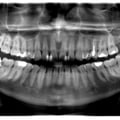

Лікування карієсу дистопованого 48 зуба не є вирішенням даної патології. Дистопія зуба мудрості провокує виникнення карієсу 47 зуба. Даний зуб має бути видалений